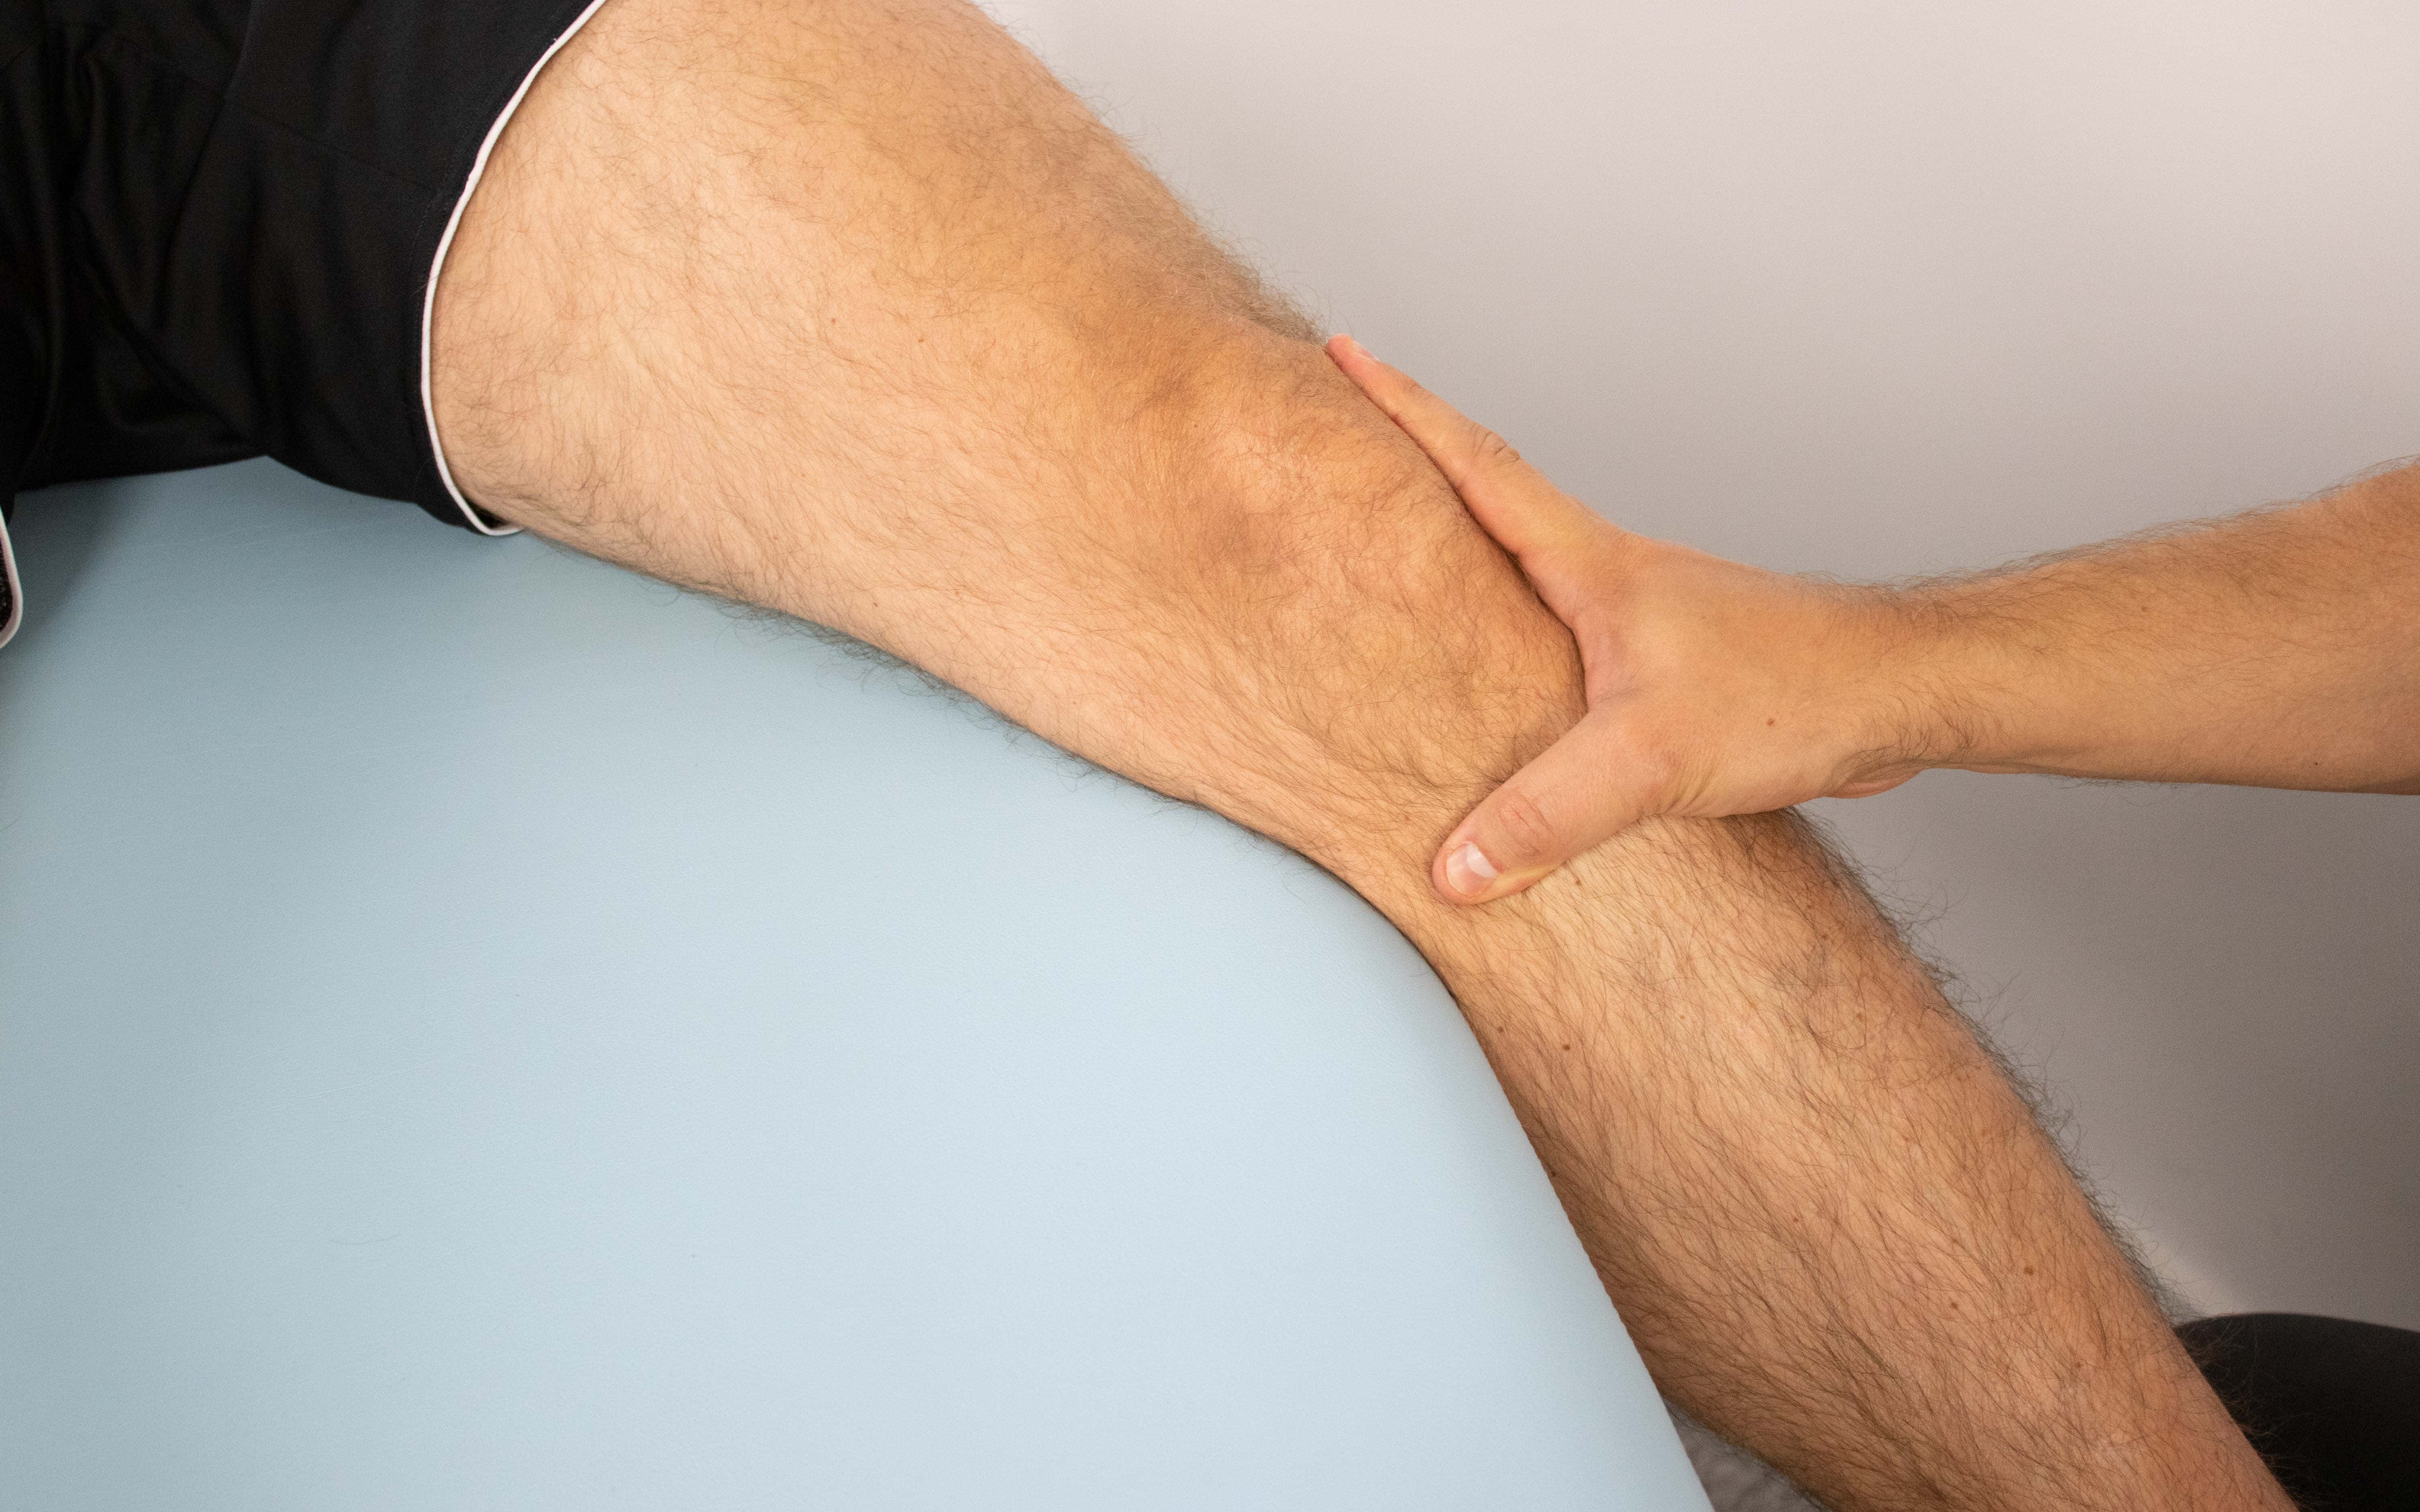

Floating Patella Test Definition . Ask you to walk around. The fluid displacement test is better for smaller effusions. Ask you to straighten and. diagnosis is made clinically in the acute setting with a patellar dislocation with a traumatic knee effusion and in chronic settings with passive. This test is also know as. perform the patellar tap test or fluid displacement test to determine the presence of fluid in the knee joint. what is patellofemoral or patellar (kneecap) instability? During the physical examination, your doctor may: Patella tap test or ballottement test is used to examine the knee swelling or knee effusion. patellar instability means the patella (kneecap) slips out of the femoral groove in the thighbone. Patients who have a tracking problem in the patellofemoral joint, where.

what is patellofemoral or patellar (kneecap) instability? Patients who have a tracking problem in the patellofemoral joint, where. diagnosis is made clinically in the acute setting with a patellar dislocation with a traumatic knee effusion and in chronic settings with passive. This test is also know as. patellar instability means the patella (kneecap) slips out of the femoral groove in the thighbone. During the physical examination, your doctor may: Ask you to straighten and. perform the patellar tap test or fluid displacement test to determine the presence of fluid in the knee joint. The fluid displacement test is better for smaller effusions. Patella tap test or ballottement test is used to examine the knee swelling or knee effusion.

Floating Patella Test Definition Ask you to walk around. diagnosis is made clinically in the acute setting with a patellar dislocation with a traumatic knee effusion and in chronic settings with passive. The fluid displacement test is better for smaller effusions. This test is also know as. perform the patellar tap test or fluid displacement test to determine the presence of fluid in the knee joint. Patella tap test or ballottement test is used to examine the knee swelling or knee effusion. what is patellofemoral or patellar (kneecap) instability? During the physical examination, your doctor may: patellar instability means the patella (kneecap) slips out of the femoral groove in the thighbone. Ask you to walk around. Ask you to straighten and. Patients who have a tracking problem in the patellofemoral joint, where.